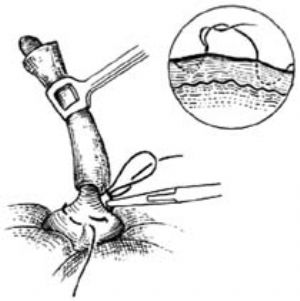

12.4 4.處理系膜

切除闌尾的操作應儘量在腹壁外進行;如有困難而需在腹腔內施行時,則應用紗布墊妥善保護好腹壁各層,以防污染。切除闌尾前,需將闌尾系膜及其中的闌尾動脈結紮並切除。如系膜較薄,炎症不重,解剖關係清晰時,可用止血鉗在系膜根部闌尾動脈旁無血管處穿一孔,拉過兩根4號絲線[圖1 ⑵],在上下相距0.5cm左右處各扎一道後切斷系膜[圖1 ⑶]。近端再結紮或縫扎一道[圖1 ⑷]。也可直接並排夾兩把止血鉗後切斷,然後再作結紮加縫扎。

圖1 ⑵結紮闌尾系膜

圖1 ⑶切斷系膜

圖1 ⑷近端加縫扎

若闌尾系膜的急性炎症較重,呈明顯縮短或水腫者,宜採用分次鉗夾、切斷法以彎止血鉗逐步鉗夾切斷闌尾系膜直達闌尾的根部,然後用4號絲線貫穿縫合結紮系膜。約半數病人的闌尾根部系膜一條來自盲腸後動脈的闌尾副動脈,應注意予以結紮。